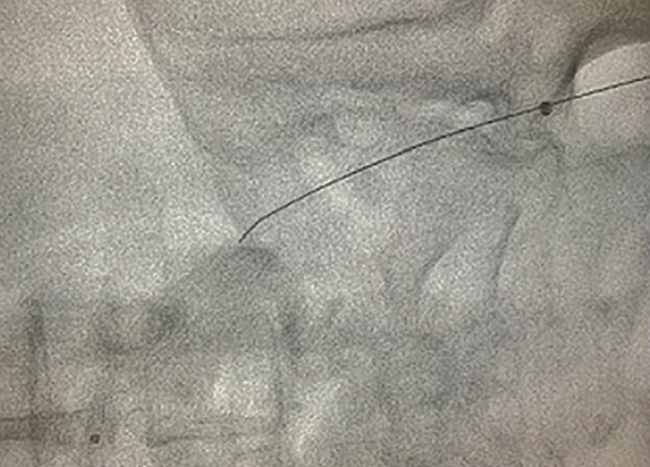

Following the angiogram, a 6 French (Fr), 45 cm sheath was inserted. An antegrade .035-inch Glidewire (Terumo) was advanced with a microcatheter to keep the knuckle small. The wire was able to enter the stent in what appeared to be a luminal fashion, but at the overlap of the two stents, the wire would prolapse behind the overlap. Stiff penetrative wires were utilized in an effort to redirect (Halberd 12 gm and Astato 30 gm [both from Asahi Intecc]). This attempt proved unsuccessful, as there continued to be prolapse between the stent overlap. After some effort, the foot was accessed with ultrasound in the posterior tibial with a 4 Fr sheath (Figure 1). A retrograde intermediate tip polymer-jacketed wire (.018-inch Gladius [Asahi Intecc]) was able to get retrograde through the stent. The antegrade-retrograde knuckles appeared to overlap and the plans was for a reverse CART. In the process of advancing an .035-inch Charger balloon (Boston Scientific) from above, the antegrade knuckle advanced and collapsed by the retrograde. A directional stiff wire (.018-inch Halberd) was able to retrograde wire into the antegrade system. The retrograde .018-inch microcatheter was advanced into the contralateral sheath. Instead of externalizing the wire, a tip in was performed (Figure 2, Video 1).

The .035-inch microcatheter was advanced from the contralateral sheath to the bifurcation and the retrograde wire was advanced into the microcatheter. The .035-inch catheter was then advanced over the retrograde wire beyond the distal cap. The retrograde wire was removed, and an antegrade .014-inch ViperWire (CSI) was advanced and externalized. The Touhy Borst adaptor was placed on the externalized wire to prevent withdrawal and allowed work to be performed over the wire in a typical antegrade fashion. A 1.5 Auryon laser (AngioDynamics) (Figures 3-4) was used to perform atherectomy for a total time of approximately 3 minutes. Following atherectomy, a 6.0 mm x 240 mm noncompliant balloon was utilized to dilate the vessel. Inflation at 4 atmospheres resulted in patient pain, but a slightly higher pressure was done at the stent overlap. Angiography revealed brisk flow through the vessel, but there was clearly dissection proximal to the previous stents. Two prolonged inflations of 5 minutes were performed without significant improvement in the dissection. A stent was subsequently placed to address the dissection, followed by postdilation with the balloon at higher pressure, which resulted in good flow through the vessel without any residual angiographic dissection (Figure 3).